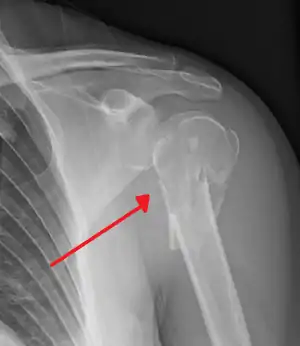

Nerves

The axillary nerve is located at the proximal end, against the shoulder girdle. Dislocation of the humerus's glenohumeral joint has the potential to injure the axillary nerve or the axillary artery. Signs and symptoms of this dislocation include a loss of the normal shoulder contour and a palpable depression under the acromion.